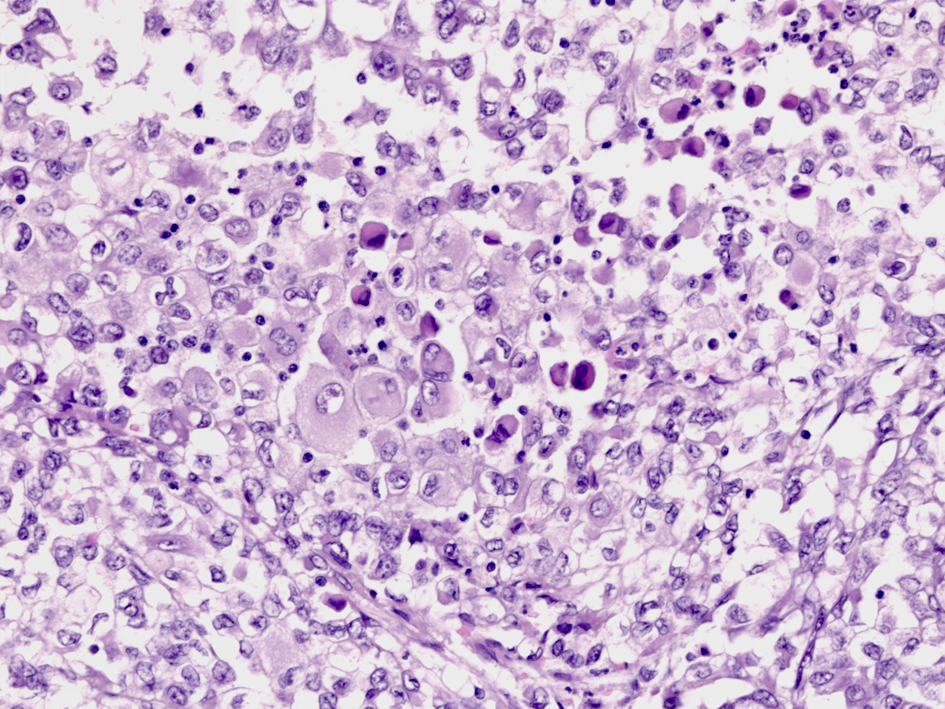

Extrarenal malignant rhabdoid tumor

組織所見:上皮様腫瘍細胞は上皮様で, 遍在する核は核小体が明瞭で濃染するクロマチンをもつ。細胞質は好酸性で豊富であり核周辺に円形, 硝子様のPAS陽性封入体がみられる. 電顕では封入体にはケラチンとビメンチンを含む中間径フィラメントの凝集が確認される。